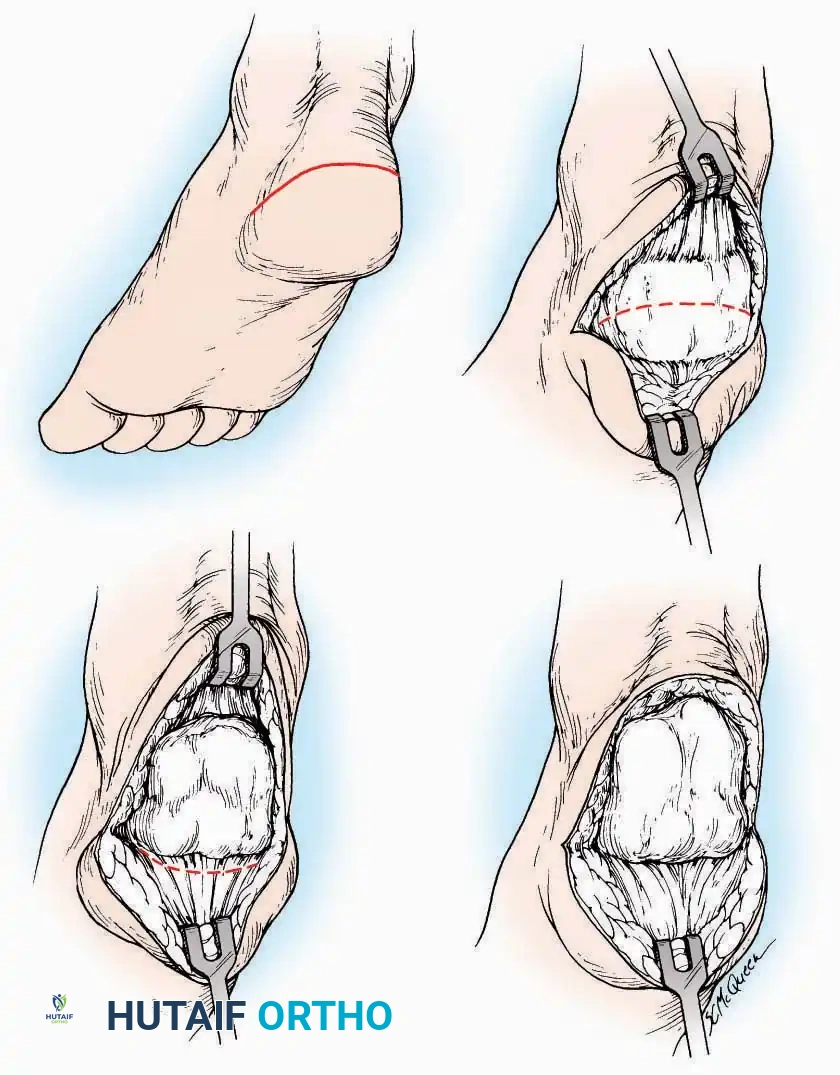

U Approach

Indications: Extensive plantar fasciotomy, radical tumor resection, or complex osteomyelitis debridement requiring access to the entire plantar surface of the calcaneus.

Positioning: Prone, with the leg supported on a large sandbag.

Surgical Technique:

* Incision: Join the medial and lateral approaches described above to form a large, continuous U-shaped incision around the posterior four-fifths of the calcaneus.

* Flap Elevation: Deepen the incision directly to bone. Elevate a massive plantar flap consisting of skin, the specialized fatty heel pad, and the plantar fascia. Retract this flap distally to expose the entire plantar calcaneal tuberosity.

Kocher Approach (Curved L)

Indications: Complete excision of the calcaneus (calcanectomy) for malignant tumors or recalcitrant osteomyelitis.

Surgical Technique:

* Incision: Incise the skin over the medial border of the Achilles tendon, starting 7.5 cm proximal to the calcaneal tuberosity. Extend it distally to the inferoposterior aspect of the tuberosity, curve it transversely around the posterior heel, and continue distally along the lateral surface of the foot to the tuberosity of the fifth metatarsal.

* Deep Dissection: Divide the Achilles tendon directly at its insertion and carry the dissection down to the bone.

* Enucleation: To reach the superior surface, free all tissues beneath the severed Achilles tendon. The calcaneus can then be enucleated subperiosteally or extraperiosteally depending on the oncologic or infectious margins required.